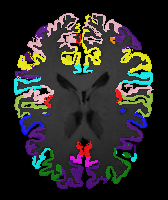

Brain MRI experiment: We also evaluate our method on the MindBooggle101 [4] brain MRIs with 32 cortical regions. We fuse corresponding segmentation labels of the left and right brain hemispheres. MindBoogle101 consists of images from multiple datasets, e.g., OASIS-TRT-20, MMRR-21 and HLN-12. After removing images with incorrect labels, we obtain a total of 85 images. We use 5 images from OASIS-TRT-20 as validation set and 15 as test set. We use the remaining 65 images for training. Manual segmentations in the N=1 and N=21 experiments are only from the MMRR-21 subset; this simulates a common practical use case, where we only have few manual segmentations for one dataset and additional unlabeled images from other datasets, but desire to process a different, new dataset. All images are 1mm isotropic, affinely-aligned, histogram-matched, and cropped to size . We apply sagittal flipping for training data augmentation. We use the same loss weights as for the knee MRI experiment except for , since cross-subject brain registrations require large deformations and hence less regularization.

Results: All trained networks are evaluated using Dice overlap scores between predictions and the manual segmentations for the segmentation network, or between the warped moving segmentations and the target segmentations for the registration network. Tabs. 1 and 2 show results for the knee and brain MRI experiments respectively in Dice scores (%). Fig. 2 shows examples of knee MRI registrations and brain MRI segmentations.

Brain results: Dice scores for segmentation and registration increase by about 2.6 and 3.5 respectively for the cortical structures of the brain MRIs.

Qualitative results: DA achieves more anatomically consistent registrations than the mono-networks on the knee (Fig. 2) and Brain MRI samples (see supplementary material).